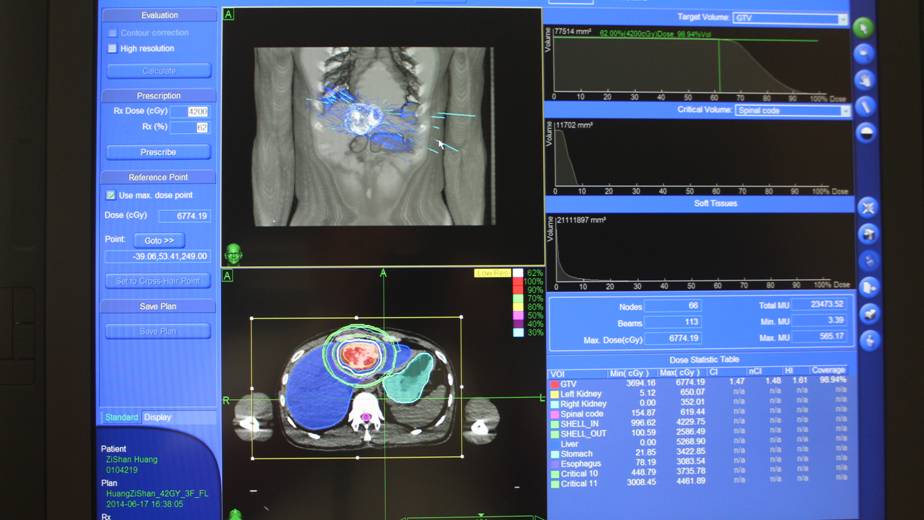

经过近一周的中医调理和准备,黄先生于16日按计划进行肝脏肿瘤定位CT扫描,数据很快被传输到射波刀治疗中心的计算机里,17日侯恩存主任在近一个小时的时间内勾画肿瘤靶区,对需要保护的胃、食管、十二指肠、脊髓、双肾、结肠等器官进行标记确认,然后对各器官给出需要和限制的剂量,下一步就由两位经验丰富的物理师在专用计算机上对治疗计划进行计算、优化。

侯恩存主任认为治疗计划符合要求:“最后各项指标均达到了我的要求。我要求的条件为尽可能使肿瘤得到破坏、正常器官得到保护。”

“除了照射时没胃口吃东西,别的没有不舒服。”黄先生对治疗过程很满意。治疗后他的症状已消失,在6月24日已带中药出院回家。以下是射波刀治疗的剂量数据和剂量曲线。

射波刀剂量数据和剂量曲线